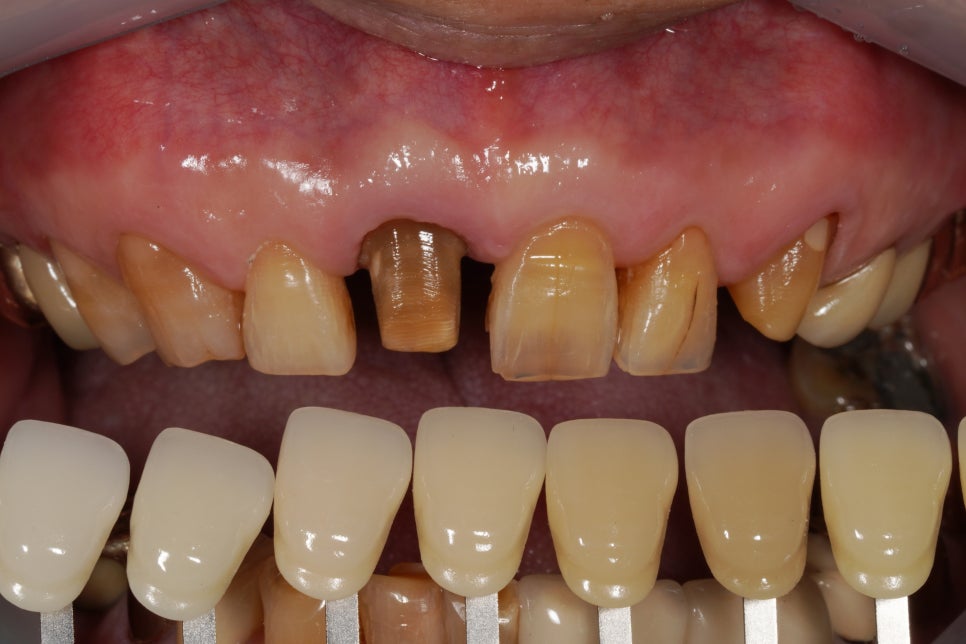

이렇게 치아 색상이 어둡게 변색된 경우에는

치아 색상을 먼저 밝게 만들어 준 뒤에

보철물을 씌우는 것이 원칙인데요

지대치 재근관치료와 실활치미백은 하지 못했습니다.

했으면 좀 더 결과가 좋았을 것 같은데 아쉽기도 해요.

그래서 그나마 치아 색상을 마스킹하기 위해

지대치 삭제에 좀 더 공을 들였습니다.

크라운을 씌울 수 있도록

치아를 다듬어 놓은 모양인데요,

치아 색상이 옆에 치아에 비해 굉장히 어둡죠,

이런 경우에는 사실

실활치 미백(신경관 안쪽에서 하는 미백)을

먼저 하는 게 좋기는 합니다.